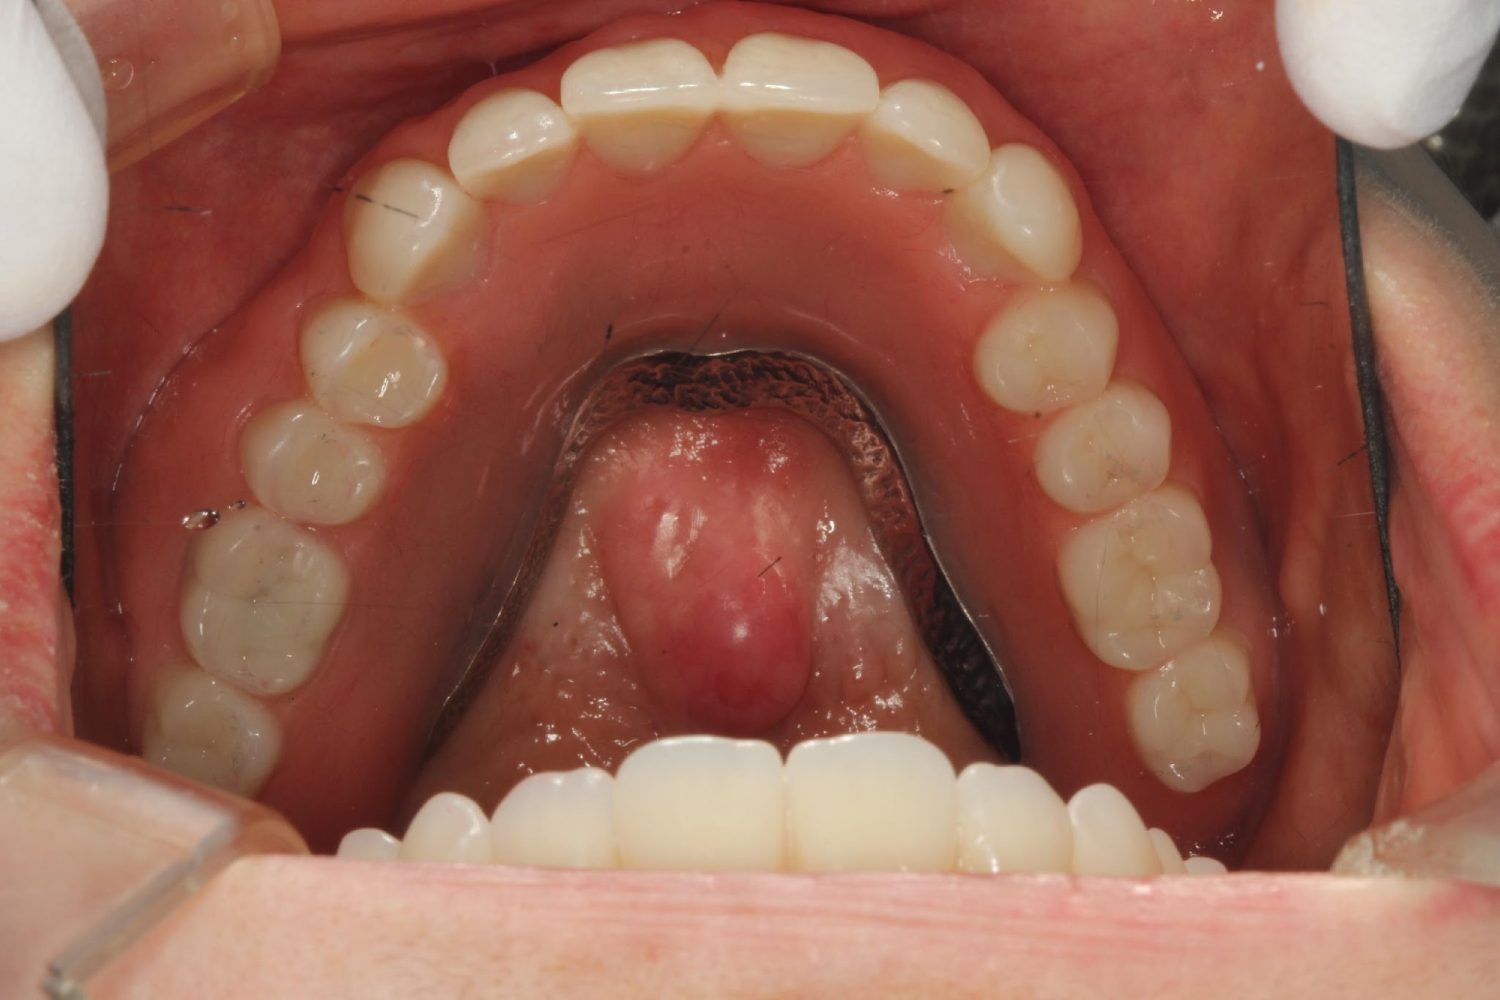

インプラント治療の症例紹介⑤

Before

After

主訴

歯肉腫脹、咬めるようにしたい

治療内容

重度歯周病により全ての残存歯保存不可能な状態。上下顎ボーンアンカードブリッジによる咬合再構成。

治療費

12,621,400円(税込)

治療期間

22ヶ月

通院回数

28回

想定されたリスク

※上部構造の形態が複雑になるため清掃が難しくなる、インプラント周囲炎の恐れがありました。

濱 仁隆先生

浜歯科

上顎8本下顎7本のインプラント体埋入によるボーンアンカードブリッジ。